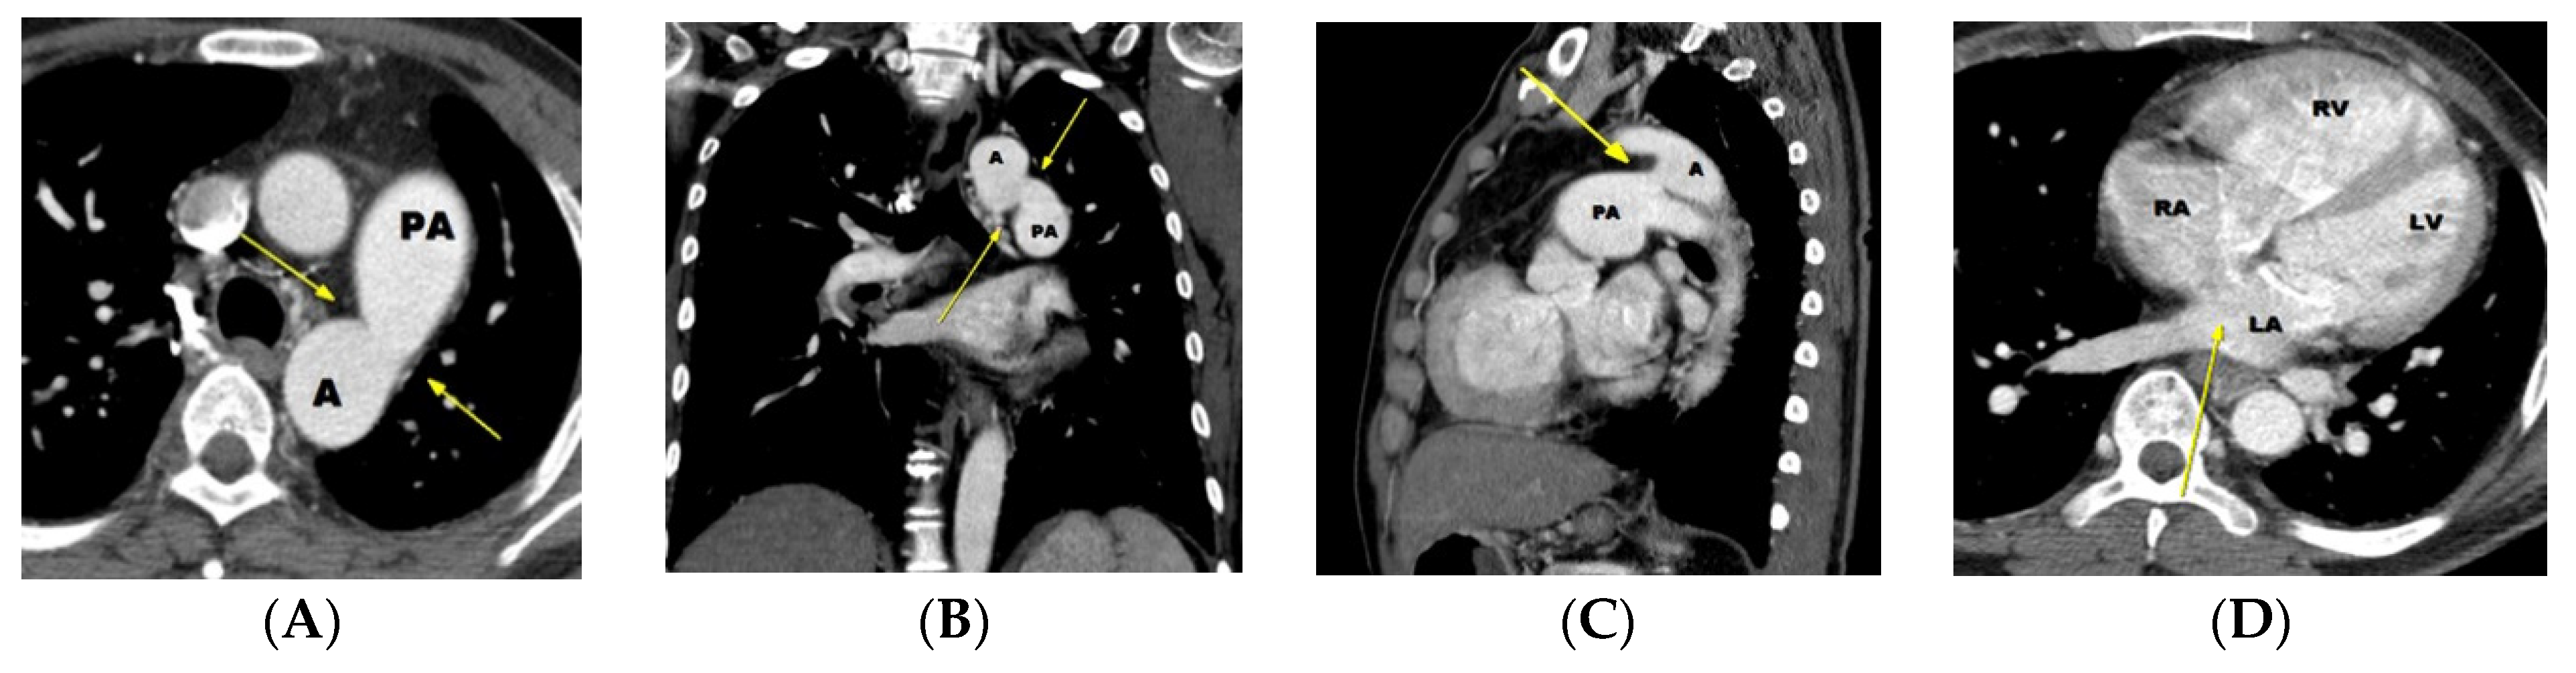

6.1. Potential Role of CT in Moderate-to Large-Sized PDA

6.2. Potential Role of CT in Small PDAs

7. Diagnostic Pitfalls of PDA on Chest CT